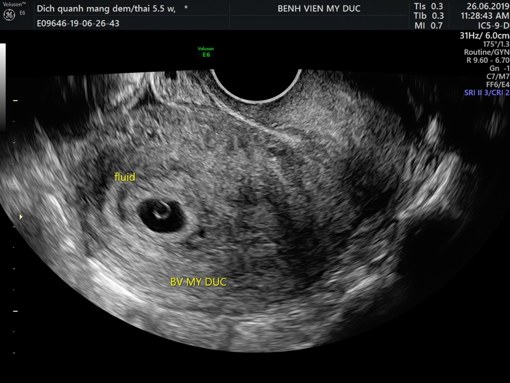

Hai cái hình bên dưới, nếu là bệnh nhân, thì khó mà hiểu hết. Nhưng nếu hỏi cái nào tiên lượng tốt hơn, câu trả lời “không biết đâu”, có nhiều chuyện trên đời, thấy vậy mà không phải vậy!!

Lớp dịch phản âm kém lượng ít dưới màng đệm có thể là dịch sinh lý ở thai giai đoạn sớm, khác với khối máu tụ dưới màng đệm. Còn nếu có xuất huyết dưới màng đệm, thì mối tương quan giữa khối xuất huyết này và kết cục thai kỳ hiện vẫn chưa rõ. Có thể có kết cục bất lợi nhưng cần nghiên cứu thêm, có thể không liên quan sẩy thai đáng kể. Ngoài ra, không có chỉ định nằm bất động trong trường hợp này, vì không cải thiện tình hình, ngược lại có khi gây hại thêm, ví dụ như tắc mạch, rất mệt mỏi, stress v.v…

Đang yên đang lành, đi siêu âm xong về không dám nhúc nhích. Túi thai tụ dịch 30%, 40%, nguy cấp lắm rồi. Nếu mà có ra máu nữa thì tình hình vô cùng bi đát!!!